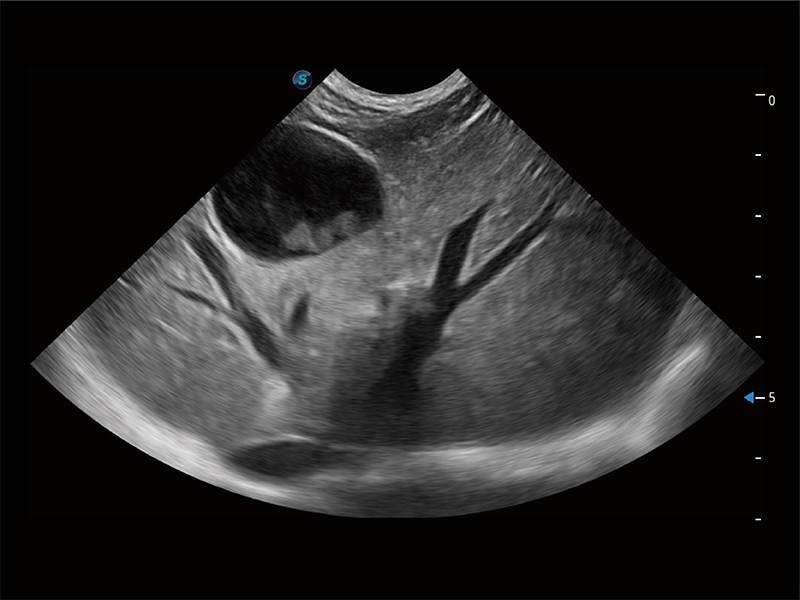

极大提升超低速微细血流的检出能力,同时更精准地滤除软组织和超声信号,为兽用医生提供以往无法通过常规血流获得的疾病诊断信息。

在传统二维血流成像的基础上,呈现血流的立体感,具有动感的生命力之美。即便是微小的血管也能轻松应对,提高了血流的视觉敏感性。